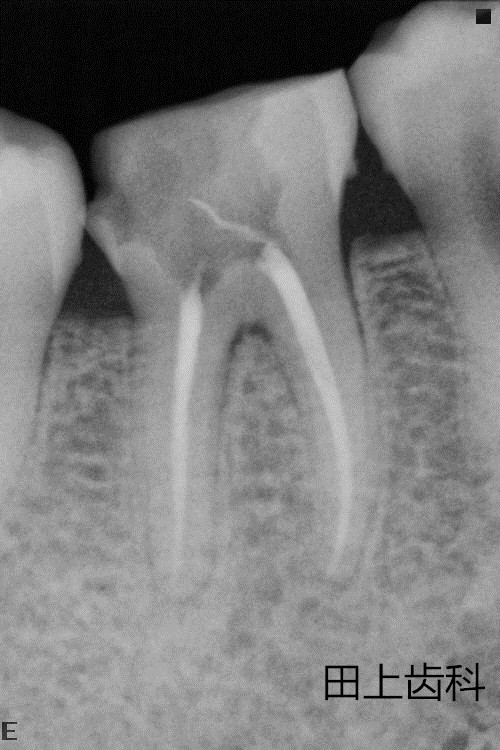

根管治疗